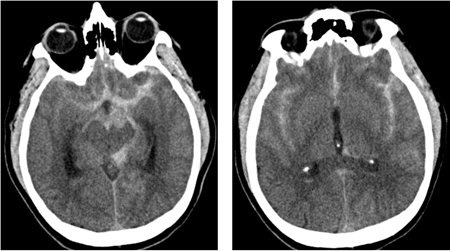

- non-contrast CT head